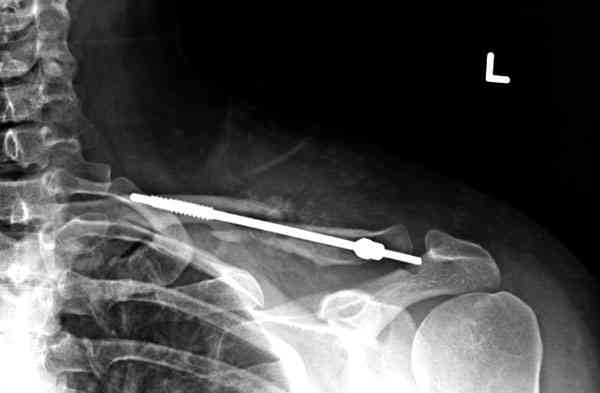

iГГШ> выполнения новокаиновой блокады дежурной бригадой выполнена закрытая

ГГШ> репозиция, наложены кольца Дельбе. Результаты репозиции показаны на

ГГШ> Результат стационарного лечения приведен на рентгенограмме (Xray_3).

Это картинка то есть через неделю после травмы, при выписке? Более чем приемлемо.